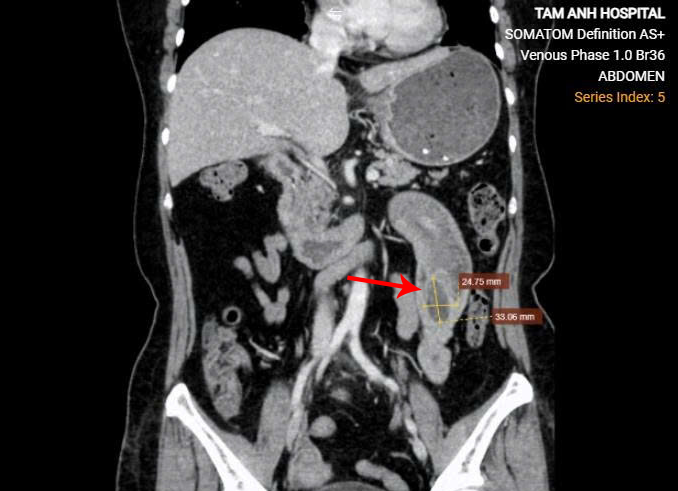

Bà Thủy uống thuốc đau dạ dày gần 5 tháng, gần đây đau bụng nặng, cấp cứu tại Bệnh viện Đa khoa Tâm Anh Hà Nội, siêu âm phát hiện khối u gây lồng đoạn ruột non dài 30 cm. ThS.BS.CKII Ngô Sỹ Thanh Nam, Phó khoa Ngoại tổng hợp, cho biết lồng ruột thường gặp ở trẻ em, ít khi phát hiện ở người lớn tuổi như bà Thủy. Kết quả chụp CT cho thấy cuối đoạn ruột lồng của bà Thủy có khối u 2,5x3 cm, vách u không ngấm thuốc, bờ đều, không thấy hạch hay các vi khối ngấm thuốc xung quanh.

Theo bác sĩ Nam, trước đây chỉ dựa vào hình ảnh siêu âm không thể đánh giá được toàn diện tình trạng lồng ruột ở người lớn, khó định hướng nguyên nhân. Hiện, các kỹ thuật chẩn đoán hình ảnh tiên tiến như CT đa lát cắt hỗ trợ phẫu thuật viên đánh giá lồng ruột ở người lớn, xác định vị trí khối lồng, tình trạng mạch máu, nguyên nhân, từ đó phẫu thuật kịp thời, hiệu quả.